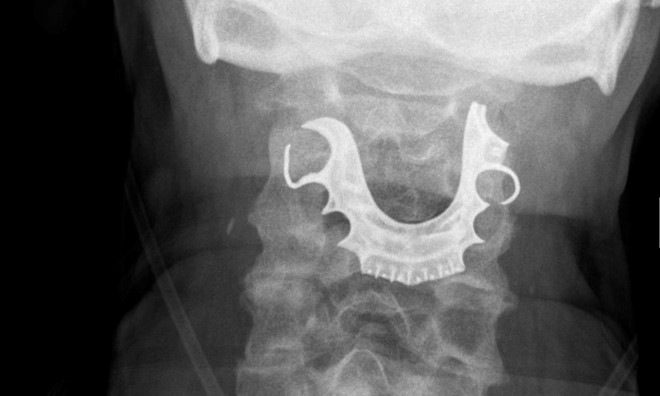

Bệnh nhân bị mắc răng giả trong cổ họng trong khi gây mê làm phẫu thuật. Ảnh: BMJ |

Đến khi nội soi, phía bệnh viện ngã ngửa khi phát hiện một vật thể hình bán nguyệt chụp xung quanh dây thanh quản của người bệnh.

“Khi đề cập chuyện này với bệnh nhân, ông giải thích rằng mình đã bị mất răng giả trong lúc phẫu thuật cách đó 8 ngày”, bác sĩ Cunniffe ghi nhận trong hồ sơ.